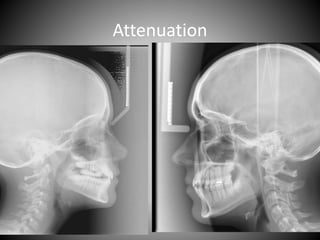

Refining - Attenuation

Attenuation